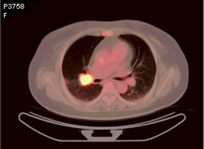

PET中文译名为“派特”,是一种非创伤性的用于探测体内放射性核分布的影像技术,其全称为:正电子发射计算机断层扫描。 医学百科网 | YxBaike.Com

传统的医学影像技术显示的是疾病引起的解剖和结构变化,而PET显示的则是人体的功能变化。换言之,如果人体的解剖结构没有发生改变,传统的影像技术对于疾病的诊断是无能为力的。实际上,疾病的发生都伴随着生化过程的功能改变,这些改变往往要早于解剖结构的改变;还有一些疾病如早老性痴呆、帕金森氏病等本身就没有明显的结构改变,传统的医学影像就无法显示这些功能方面的变化了。 医学百科网 | YxBaike.Com PET能得天独厚地显示功能性的改变,因而对疾病的更早期发现、诊断具有无与伦比的优势;此外,PET还能进行三维立体动态及全身显像,可发现其它检查所不能发现的问题,防止了“—叶障目,不见泰山”,弥补了传统医学影像的不足。